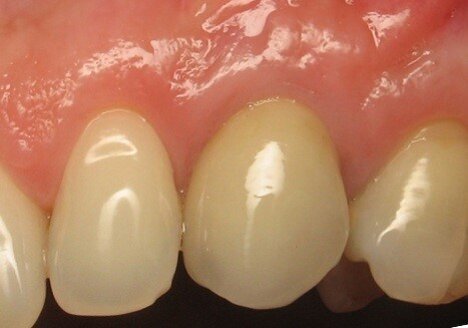

Imedijatna ugradnja implantata smanjuje broj hirurških intervencija i redukuje vreme potrebno da se izvede celokupni tretman. Idealno trodimenzionalno pozicioniranje implantata, očuvanje alveolarne kosti, sa posebnim akcentom na bukalnu koštanu lamelu, kao i zadovoljavajući izgled mekog tkiva mogu biti postignuti ovom procedurom. Mogu se očekivati visoki estetski rezultati.

Dugoročno preživljavanje implantata, i zdravlje tkiva koje ga okružuju, ne ispunjavaju zahteve koji se postavljaju pred savremenu implantologiju. Danas smatramo da je estetski učinak podjednako bitan za uspeh implantata. Ugradnja implantata i protetska rehabilitacija su posebno izazovne u esteskoj zoni. Detaljna analiza parametara neophodnih za idealno pozicioniranje implantata, kao što su dijagnoza, plan terapije, anatomski parametri, trodimenzionalno pozicioniranje, kao i dizajn implantata su od presudnog značaja za uspeh ove procedure.